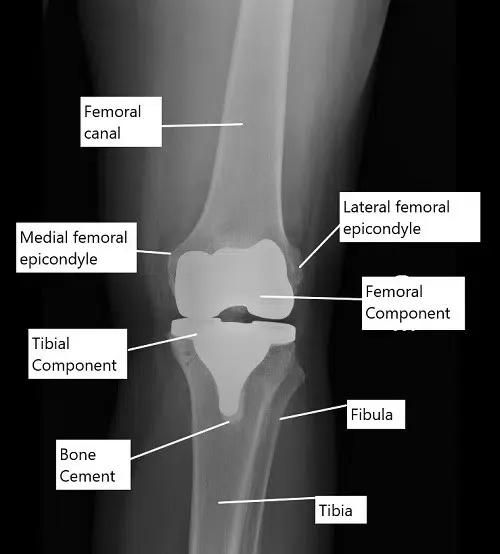

X-ray showing a total knee replacement in AP view.

Knee replacement surgery is most commonly done to treat end-stage osteoarthritis. During the surgery, the bony ends forming the knee joint are replaced with metal alloy prosthetic parts. The lower end of the femur is replaced with a femoral component and the upper part of the tibia is replaced with a tibial component.

The size of the prosthetic metal implants is determined by the size of the bone removed during the surgery. The surgeon cuts the bone to remove the arthritic bone and as well as to correct any deformity caused by arthritis. The implants are capped at the bony ends using special bone cement.

The undersurface of the kneecap (patella) is usually covered by a prosthetic plastic part. A polyethylene plastic spacer is introduced in between the metal parts to smooth the movement and provide stability.